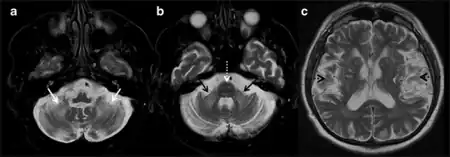

Clinical findings are divided into major and minor symptoms. Major symptoms include intention tremor and gait ataxia. Minor symptoms such as parkinsonism, short-term memory deficit, and executive function decline can further contribute to a diagnosis of FXTAS. Radiological findings are similarly divided into major and minor categories. As patients with FXTAS can have distinct brain scans from other movement disorders, a scan showing white matter lesions of the middle cerebellar peduncle is a major finding that can be attributed to FXTAS. Overall or generalized brain tissue atrophy and cerebral white matter lesions can also be minor indicators for a diagnosis.[12]

For a definite diagnosis to be made, a major radiological finding and one major clinical finding must be present. Probable diagnosis is based on the presence of either a major radiological finding and a minor clinical finding, or two major clinical findings alone. The possible category for diagnosis can be made with a minor radiological finding and a major clinical finding.[12]